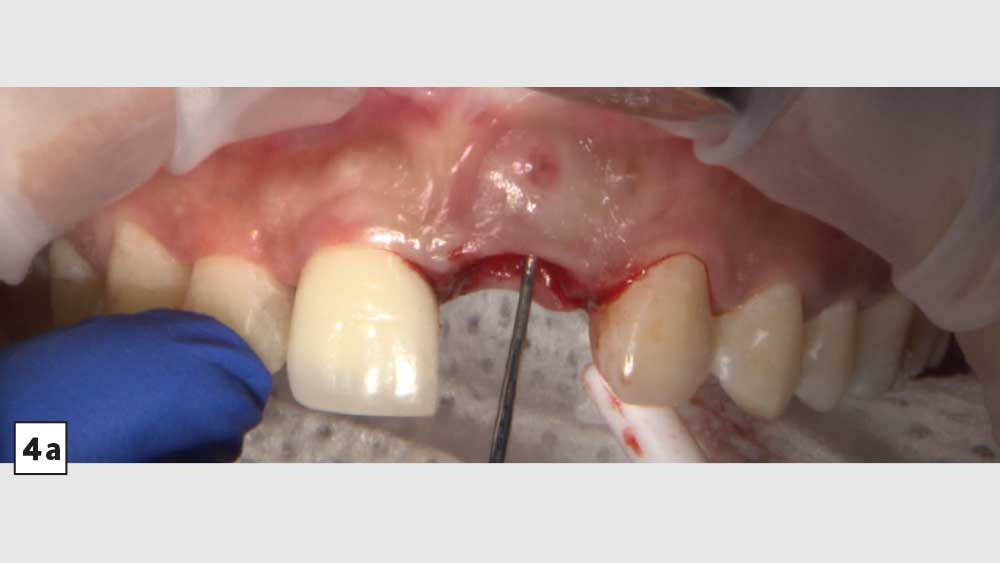

BRIDGING THE GAP WITH BRUXZIR® ESTHETIC

After conducting a thorough diagnostic examination, a vertical root fracture was noted, leaving the #9 central incisor malaligned and unstable. Due to the presence of significant vertical bone loss, extensive treatment for guided bone regeneration and a connective tissue graft would have been required prior to implant placement. After the patient was consulted on these factors, she opted against implant treatment. Once we discussed the remaining options, she decided on a bridge from #8–11 and a veneer on #7. Because she was congenitally missing tooth #10, placing a bridge to restore the edentulous area required preparing the adjacent canine and reshaping it to look like the missing lateral. I selected BruxZir® Esthetic Solid Zirconia as the best material to restore her beautiful smile. Not only does BruxZir Esthetic have superior strength compared to similar all-ceramic materials such as IPS e.max®, but it also has a translucent, natural-looking appearance. Sometimes clinicians think it is risky to do an all-ceramic bridge, but with a strong material like BruxZir Esthetic that has an average flexural strength of 870 MPa, doctors can confidently seat an anterior bridge that will produce long-lasting results. BruxZir has become such a popular material for dentists that it has been utilized to successfully fabricate more than 1.2 million bridges.